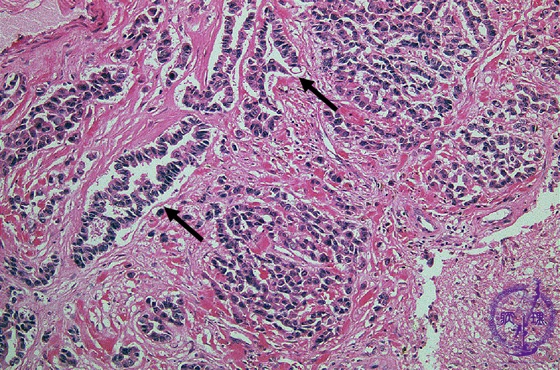

- (10)Metastatic brain tumor

Microscopic findings (H.E. high magnification): Tumor cells showed apparent glandular structures (arrows), indicating the brain metastasis of adenocarcinoma (from lung).